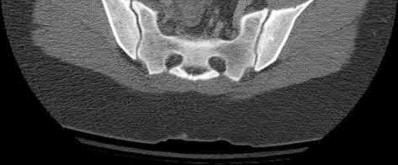

2. # A 35-year-old woman is involved in a head-on collision while driving. Initial radiographs are shown in Figures 8a and 8b. Injury to what vessel increases the risk for osteonecrosis of the injured bone?

5. Artery of the tarsal sinus Corrent answer: 4

The patient has a Hawkins type III talar neck fracture-dislocation with a risk of osteonecrosis ranging from 69% to 100%. Anatomic studies have shown that the artery of the tarsal canal supplies the lateral two thirds of the talar body.

The other vessels listed provide no significant contribution to the talus.